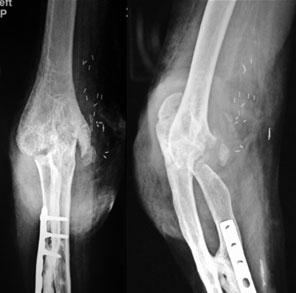

Xrays after surgery

The distal humerus has been shaped into a notch with the olecranon shaped into a hook creating two congruent surfaces and a flexion-extension axis.

The functional outcome after 2 months of surgery. The post surgery arc of motion was 120 degrees with an extension of 20 degrees and flexion up to 130degrees.